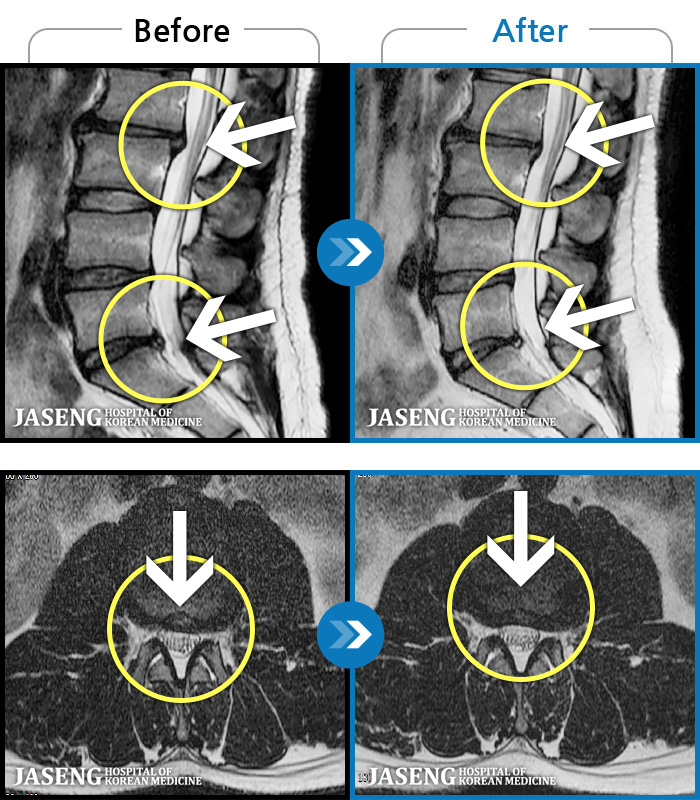

MRI ġ

1,299 MRI ũ ʸ Ȯϼ.